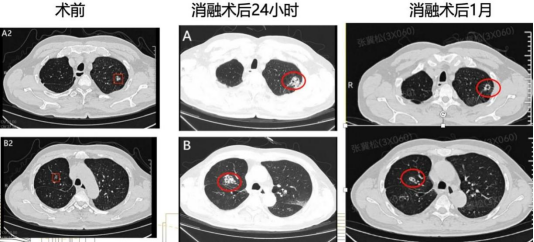

何大伯的双肺CT影像

术后24小时复查CT显示,双肺病灶消融充分,完全覆盖目标结节,且没有出现气胸、出血等并发症。得益于这项技术的精准性和安全性,何大伯第二天就顺利出院了。更令一家人庆幸的是,随后的病理结果确诊为双原发肺腺癌,而由于发现及时并通过微创手术获得根治,何大伯不仅避免了传统手术的痛苦,更无需承受后续放化疗的负担。